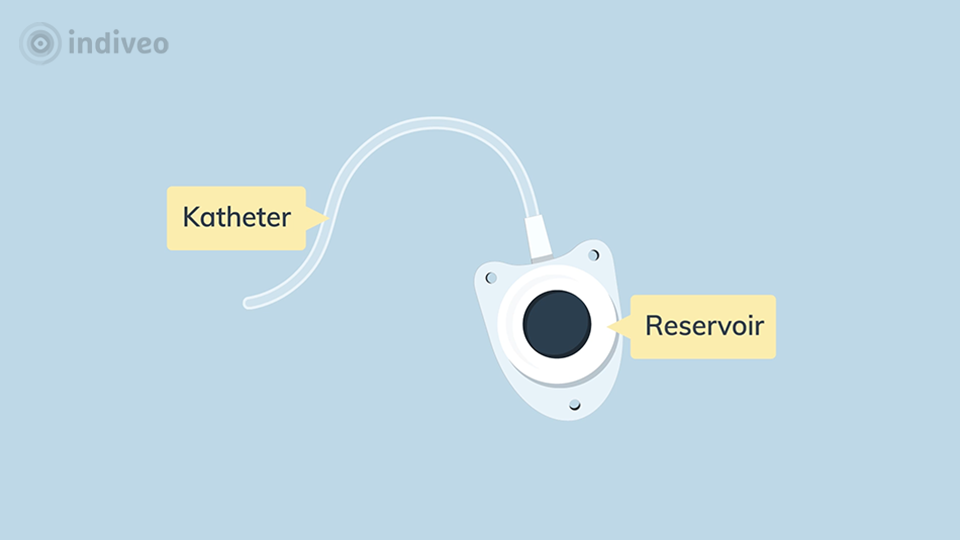

In deze Divi krijgt de patiënt uitleg over wat een port-a-cath is en waarom deze wordt geplaatst. De patiënt ziet dat dit een klein reservoir onder de huid is dat via een slangetje in een bloedvat ligt, waardoor medicijnen of vocht gemakkelijk toegediend kunnen worden en bloed kan worden afgenomen. Ook wordt uitgelegd hoe de plaatsing verloopt, hoe de port-a-cath gebruikt wordt tijdens behandelingen en waar de patiënt op moet letten in het dagelijks leven.